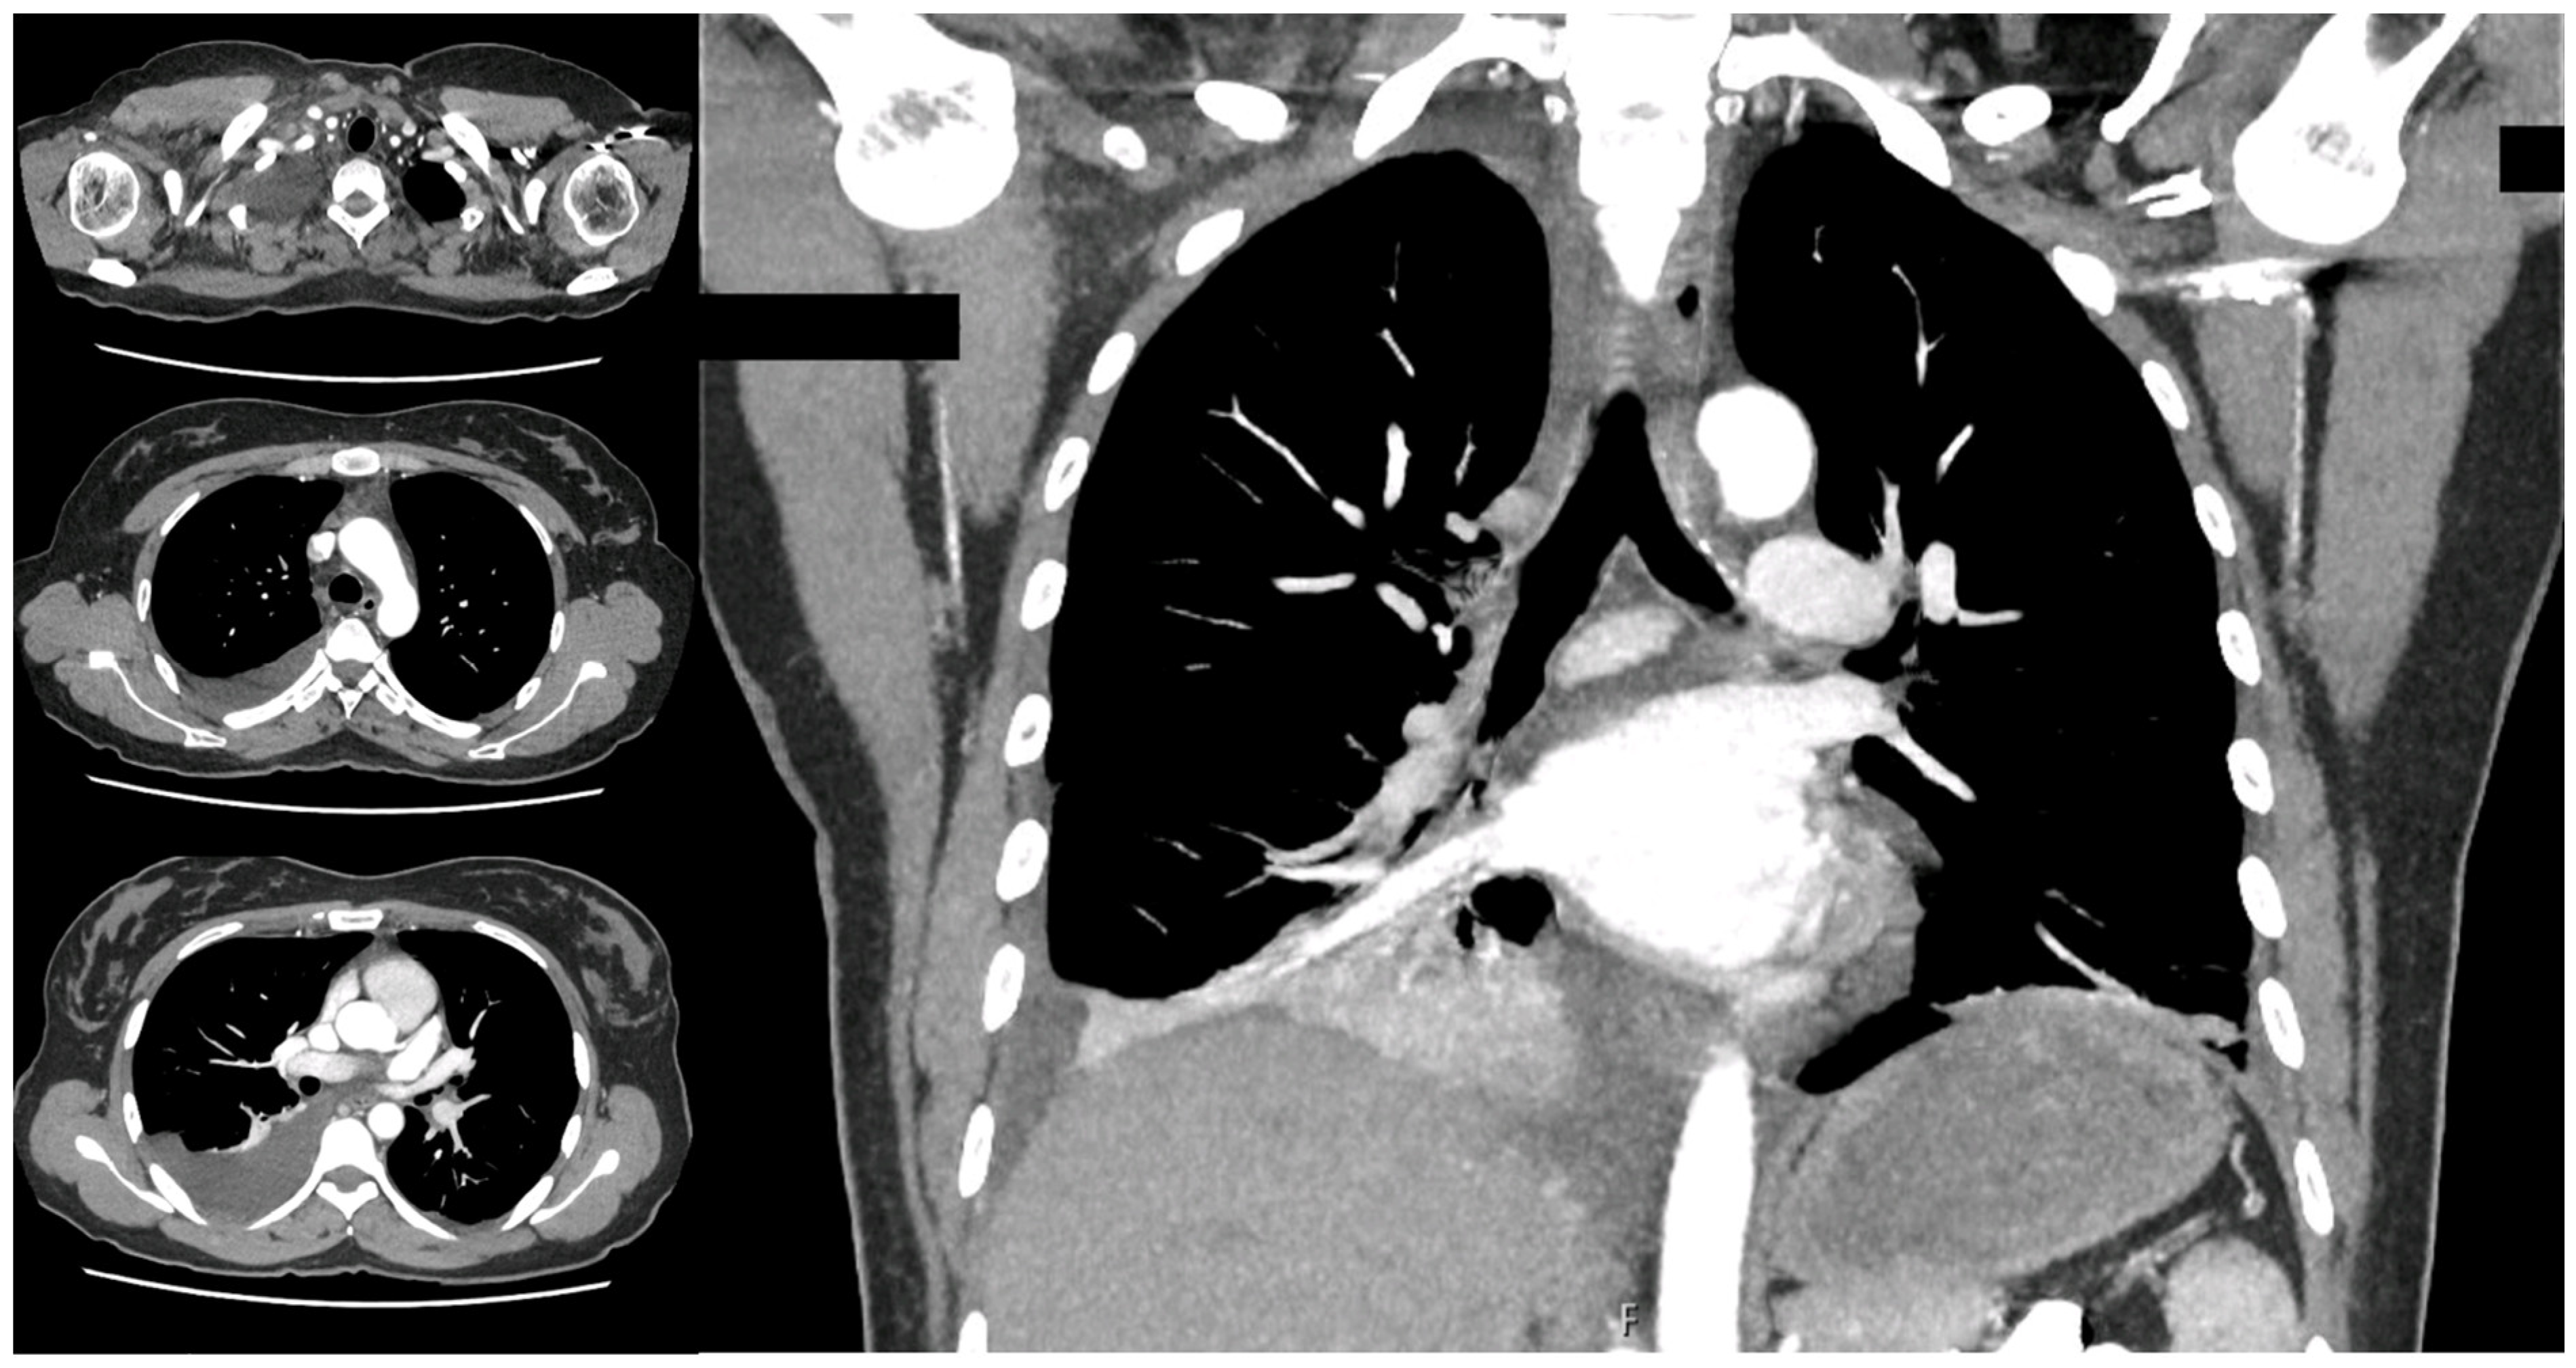

2. Case Presentation